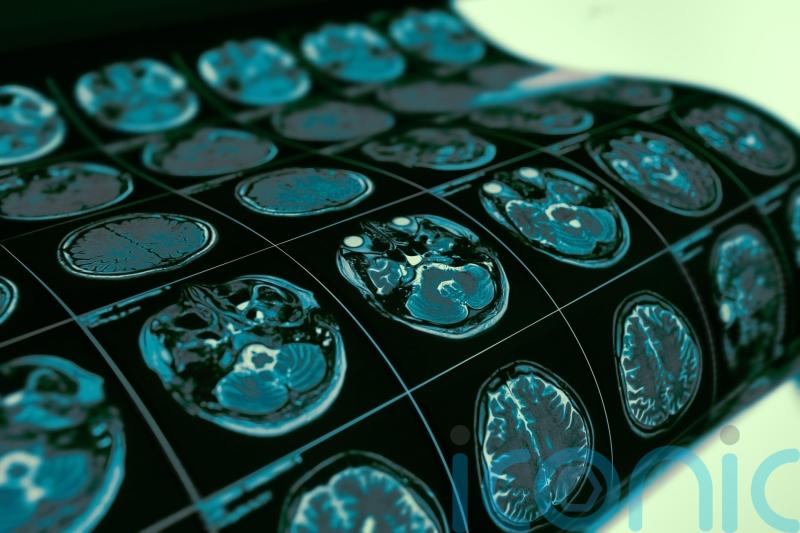

On Monday, he wrote on X to say he had an MRI scan last week and there was still no sign of recurrence.